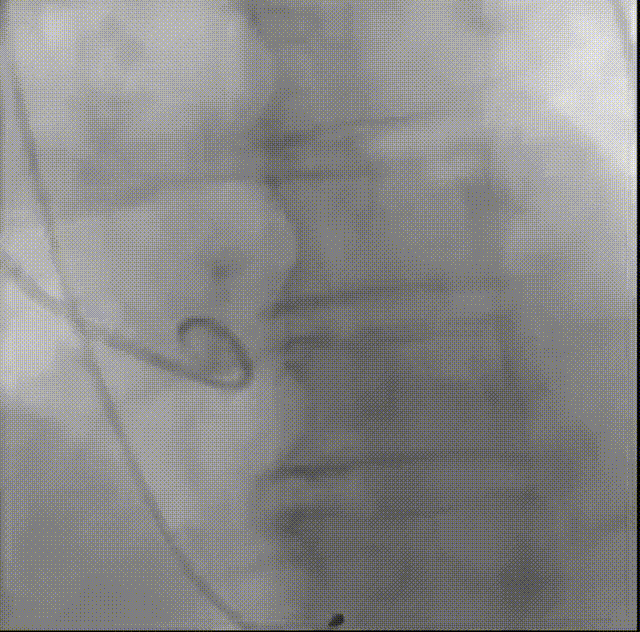

罗建方教授 广东省人民医院(点击查看专家详细简历) 设计本为临床需,耐久守护好芳华:任何医疗产品的设计初衷与最终归宿,都应落在 “临床获益” 这一核心上。尤其在 TAVR 领域,年轻患者预期寿命长,术后瓣膜的长期性能直接关乎其生活质量与生存预后。瓣膜耐久性问题,是落到临床实践中亟待突破的关键课题。传统瓣膜在长期使用中,可能因结构老化、功能退化等问题,难以满足年轻群体数十年的健康需求,二次手术风险也随之攀升。因此,产品设计必须直面这一临床痛点:通过材料革新增强抗钙化性能及生物相容性,以技术突破延长瓣膜有效使用寿命。此次临床应用的预装干瓣Prostyle A®是TAVR领域的革新理念,干瓣预期会为临床提供更耐久性的保障,实现了与临床需求的精准对接,为年轻群体的瓣膜治疗提供更坚实的保障。 李捷教授 广东省人民医院(点击查看专家详细简历) 干瓣技术求革新,性能兼顾护临床:干瓣的技术革新在创新的同时需要和临床实际需求深度耦合,兼顾TAVR术中的核心考量点。临床操作中,瓣膜能否顺利过弓,直接影响手术效率与安全性。Prostyle A®短瓣架设计及第二台阶的柔顺设计,术中操作丝滑;同时,瓣膜植入后的径向支撑力必须平衡得当,才能实现稳定锚定;释放后造影显示:瓣膜形态舒展,轻度瓣周漏,舒张压升高,冠脉开口未受影响;瓣周漏是影响术后效果的关键隐患,双层裙边设计通过多重密封机制降低反流风险,为患者长期获益筑牢防线。这些性能的协同优化,最终目的是让干瓣在临床中真正做到 “好用、耐用、安全用”,为患者预后提升提供坚实支撑。 患者病史 患者因 “活动后气促伴头晕 2 月” 入院。 现病史:2月前无诱因出现活动后气促,休息后缓解,伴头晕,夜间阵发性呼吸困难。超声检查发现:主动脉瓣重度狭窄并重度返流(跨瓣流速 4.3m/s,峰值压差 73mmHg);主动脉 + 冠状动脉 CTA 提示主动脉瓣显著钙化,升主动脉及分支粥样硬化,冠状动脉轻度狭窄(RCA 狭窄 30-40%)。 既往史:高血压病史 15 年,规律服药,血压控制稳定。 术前诊断:非风湿性主动脉瓣狭窄伴关闭不全(重度)、心功能 II 级(NYHA)、高血压病 2 级(高危)、冠状动脉粥样硬化。 术前CT 三叶瓣,瓣叶增厚中度钙化,右无交界钙化粘连,瓣环径25.1mm,LVOT 25.1mm,直筒型结构;窦部空间足够,升主未见增宽,瓣环水平夹角55°;冠脉开口位置佳,无冠脉风险;入路散在钙化、外周双侧入路无明显迂曲,双侧内径可、中分叉,左右侧均能够支持20F 大鞘通过。 造影角度及入路 手术策略 右侧股动脉为主入路,左侧为辅助入路;使用20球囊预扩,准备AV26瓣膜,冲洗口朝向3点钟方向送入输送系统性能,初始定位真实瓣环0位释放,最终锚定约瓣下3mm,工作位评估瓣膜稳定性与冠脉情况。 手术过程 根部造影 20mm 球囊预扩无明显腰征 术中使用26号瓣膜,瓣膜释放贴边迅速 80% 工作位观察瓣膜位置良好 释放后造影显示:瓣膜形态舒展,轻度瓣周漏,舒张压由术前30mmHg升为 60mmHg,冠脉开口未受影响。 术后超声:跨瓣流速降至1.6m/s,平均压差降至5 mmHg,心功能显著改善。 Prostyle A®预装干瓣——助力临床最优化解决方案: 1. 抗钙化与耐久性:Micro-EX™专利技术提升瓣膜抗钙化能力,适配患者瓣叶中度钙化的解剖特点,为长期疗效提供保障。 2. 柔顺过弓与精准定位:短瓣架设计 + 远端超滑涂层,确保患者输送系统过弓顺畅;瓣架流入端微直筒设计,让定位贴边更迅速,减少了手术时间; 3. 80% 可回收设计:便于术中调整观察,减少起搏时间,从而减少并发症。 4. 简化手术流程:预装设计缩短操作时间,20F 大鞘兼容外周入路,降低血管损伤风险。 · END ·